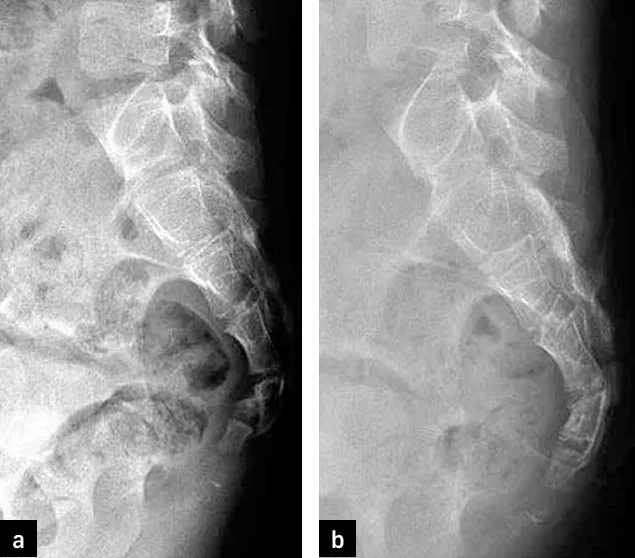

Outre les fractures, l’activité sportive peut être responsable de coccygodynies liées à une instabilité coccygienne par luxation (figures 19a et 19b), nécessitant un examen radiologique de profil en position debout puis assise, à une arthrose coccygienne ou à une épine coccygienne (92) pouvant engendrer une bursite (figure 20).

Figures 19a, 19b et 20 : luxation postérieure du coccyx [19a et 19b] (© Coll JM Didelot) et épine coccygienne [20] (92)